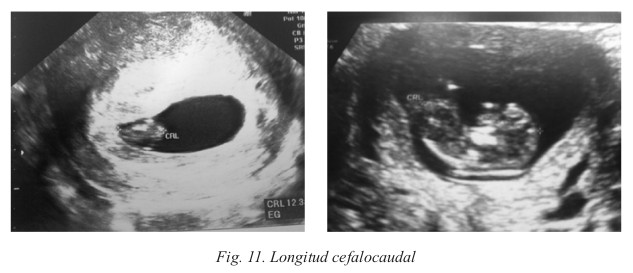

A partir de las 7 semanas podemos diferenciar el polo cefálico, las extremidades y la bolsa amniótica del embrión; alcanzando éste los 25-27 mm de tamaño (Fig. 11). En este momento, el parámetro óptimo para datar la gestación es la medición de la longitud craneocaudal. A partir de la semana 12, se utilizará la medición del diámetro biparietal (Fig. 12) para conocer la edad real del embarazo, y en la semana 20 la longitud del fémur (Fig. 13).